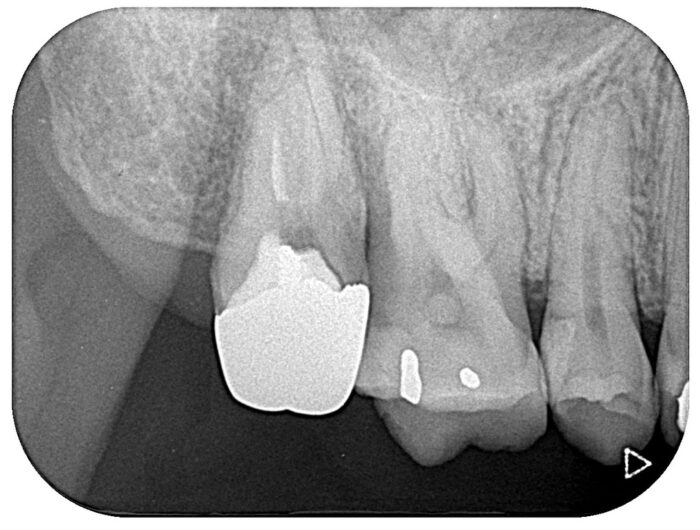

その後、元の位置へ再植し、適切な固定を行いました。

術後は大きなトラブルなく経過し、1年後の時点で以下の状態を維持しています。

自覚症状なし

ルートトランク形成なし

しっかり噛める状態

処置直後

術後1年

ほとんど右上7(一番左端の歯)歯の周りに骨が出来上がっています。